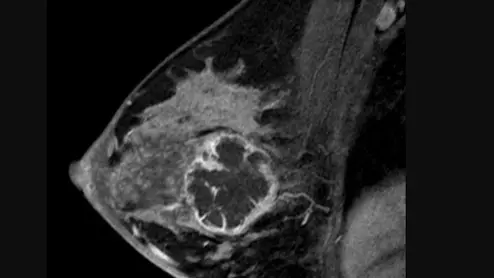

Sagittal images from breast MRI in a 36-year-old woman with an invasive ductal carcinoma. Image from pre-chemotherapy contrast-enhanced T1-weighted MRI shows a round, rim-enhancing mass. This  subtraction image shows the maximal diameter of the mass was measured up to 5.4 cm. Read more. RSNA image. What does breast cancer look like?